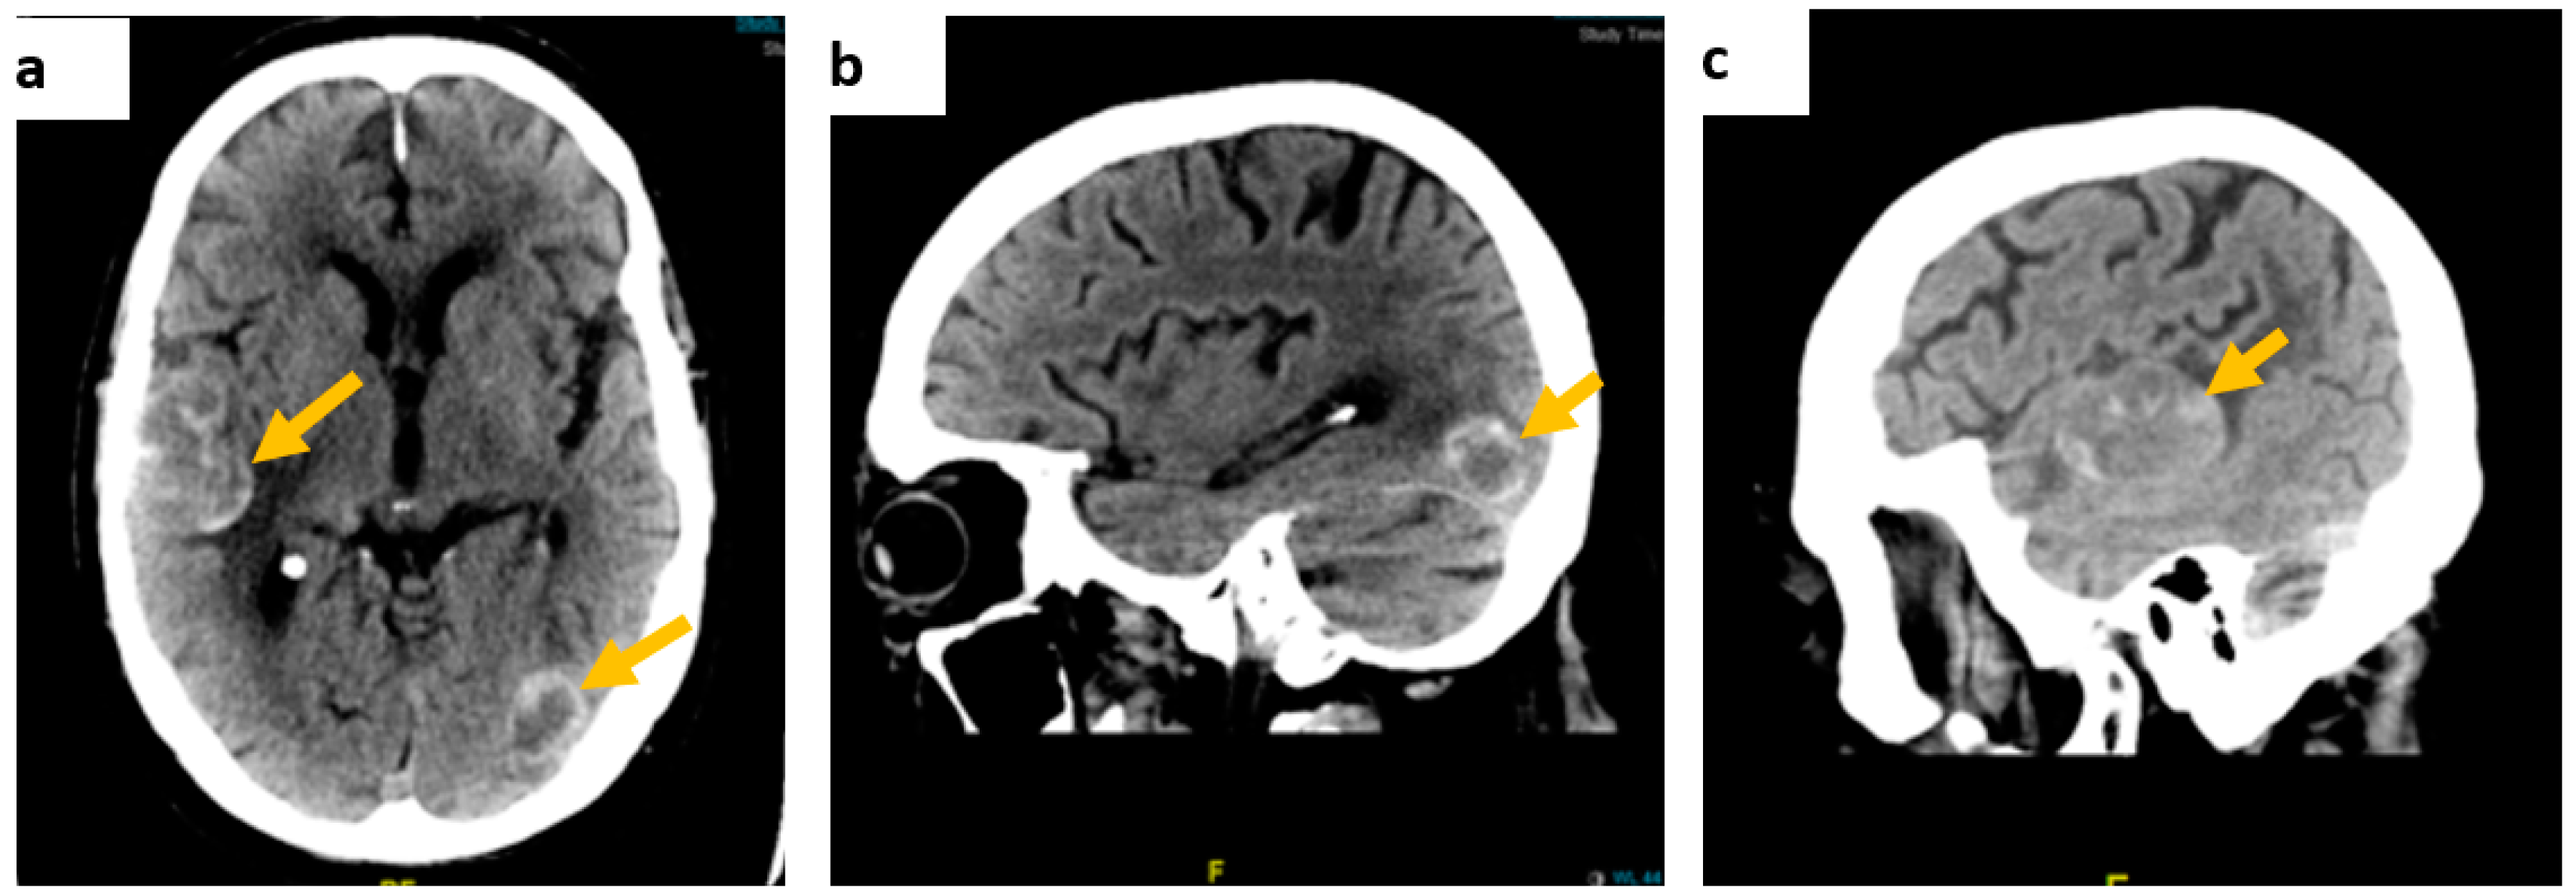

Contrast-enhanced CT of the brain showed multiple intra-axial dense space-occupying lesions in keeping with haemorrhagic metastases (Figure 1).

Figure 1.

Contrast-enhanced brain CT scan images. (a) On axial view, a right temporoparietal lobe lesion measuring approximately 54 × 33 mm and a smaller left temporal lesion, (b) on sagittal view, a left occipital lobe lesion, measuring approximately 23 × 18 mm, and (c) the right temporal lesion on the sagittal axis.

The neuro-oncology multi-disciplinary team meeting concluded that, due to widespread metastatic cerebral disease, surgical intervention was not feasible and a palliative care referral to a hospice was made. The patient subsequently presented with further seizures and aspiration pneumonia, with contrast-enhanced CT of the brain showing interval increase in size on the previously detected lesions (Figure 1). Following mild clinical improvement, he opted to be discharged home with community palliative care support. Further to this, molecular analysis of the lymph node biopsy showed approximately 60% neoplastic nuclei. No mutations were detected in the regions analysed within the BRAF and KIT genes however an NRAS mutation was detected. At this stage, a decision to start him on an immune checkpoint inhibitor was made with ongoing palliative care support for symptoms.